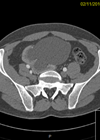

In the sixth article in this series the authors describe endourology nightmares involving ileal conduits and calculi. Case 1 A 69-year-old man who had a cystectomy and ileal conduit for muscle invasive bladder cancer, presented with an acute kidney injury...